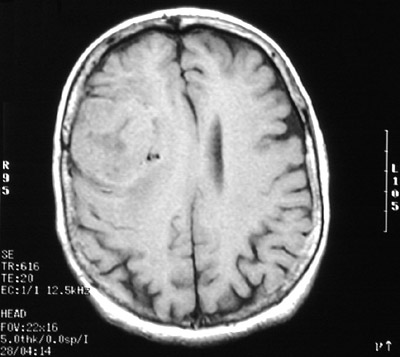

This MRI scan in axial view above and sagittal view below demonstrates a meningioma in the parasagittal region over frontal lobe.